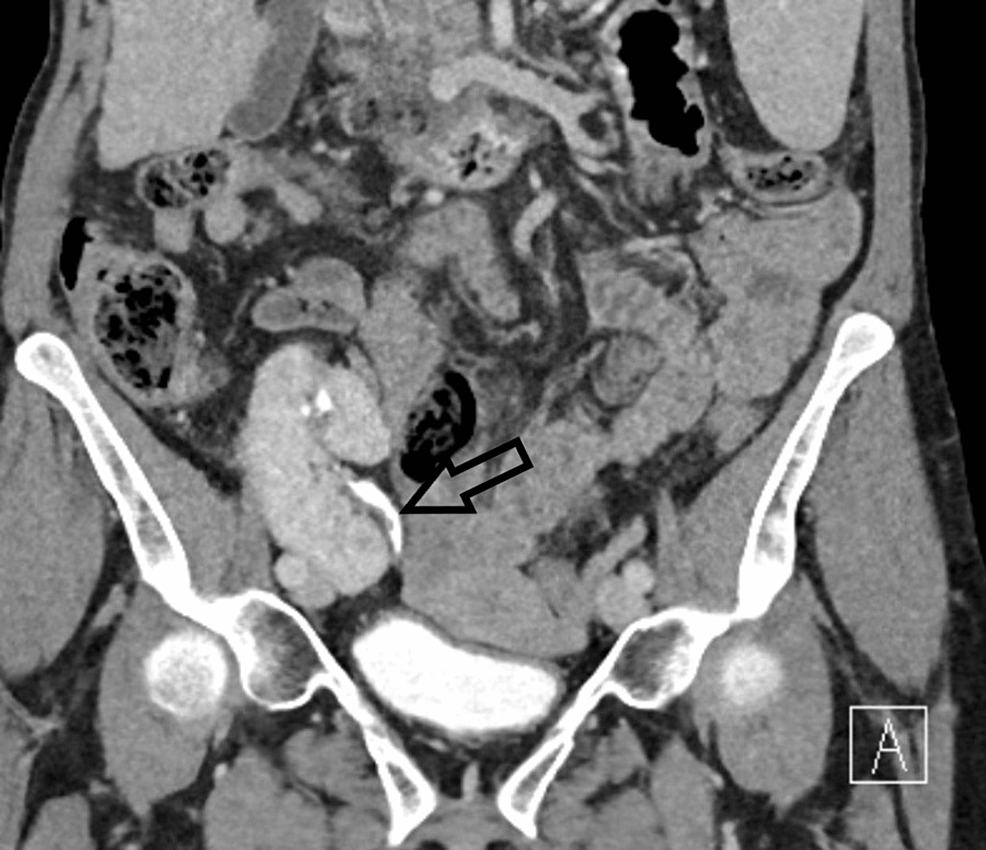

CT scan coronal view with left ureter 2 mm stone (arrow) American Radiolucent Stone In Ct Patients with kidney stones who have a urinary ph of 5.5 or less and whose stones are about 500 hounsfield units or less can reliably be diagnosed as having uric acid. Kidney stone disease (nephrolithiasis) is a common problem in primary care practice. Pure uric acid calculi are radiolucent on radiography but can be readily identified on ct. Transverse unenhanced. Radiolucent Stone In Ct.